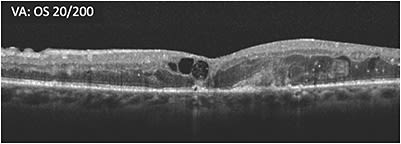

A 65-year-old male patient with proliferative diabetic retinopathy (PDR) who had undergone vitrectomy for nonclearing vitreous hemorrhage presented 2 months later. OCT showed substantial cystoid macular edema and hyperreflective foci (A) and he had poor vision (20/200 OS). The patient was started on treatment. Three months later, the retina was less swollen, but some macular edema remained, vision was 20/200, and cystic changes persisted (B). Treatment was switched within the same class in an effort to address the remaining macular edema. At 4 weeks following the initial treatment with the second therapy, vision remained poor (20/200 OS) and cystic spaces remained (C). Over the course of the next 8 months, the patient received 8 more treatments with the second therapy. Visual acuity was 20/100 -2 while the appearance of the cystic edema on OCT worsened (D).

Treatment was then switched to a different class of therapy, which led to 20/63 -2 visual acuity after the first treatment and improvement in the retinal anatomy. Somewhat unexpectedly given subretinal scarring due to lipid deposition near the fovea (but preservation of the outer retinal bands [E]), vision eventually stabilized at 20/40 with continued treatment.